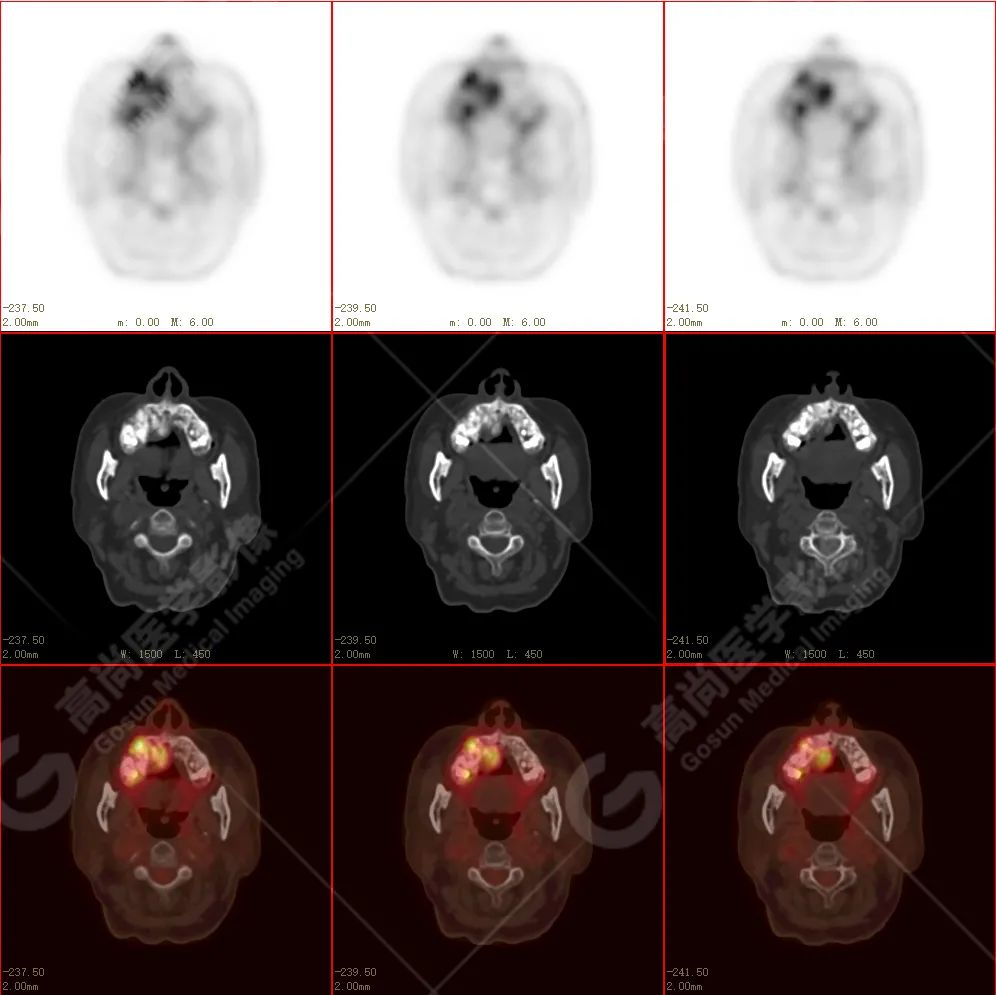

右侧上颌骨-上颌窦骨壁-骨性鼻中隔区域见片块状放射性摄取异常增高影,最大层面约 4.1 cm×3.8 cm×2.8 cm,SUV 最大值为 10.4,CT 示上述部位见成骨性改变,骨质不均匀弥漫性增厚、密度不均匀增高,并可见肿瘤骨影,边缘毛糙,周围伴软组织增厚。